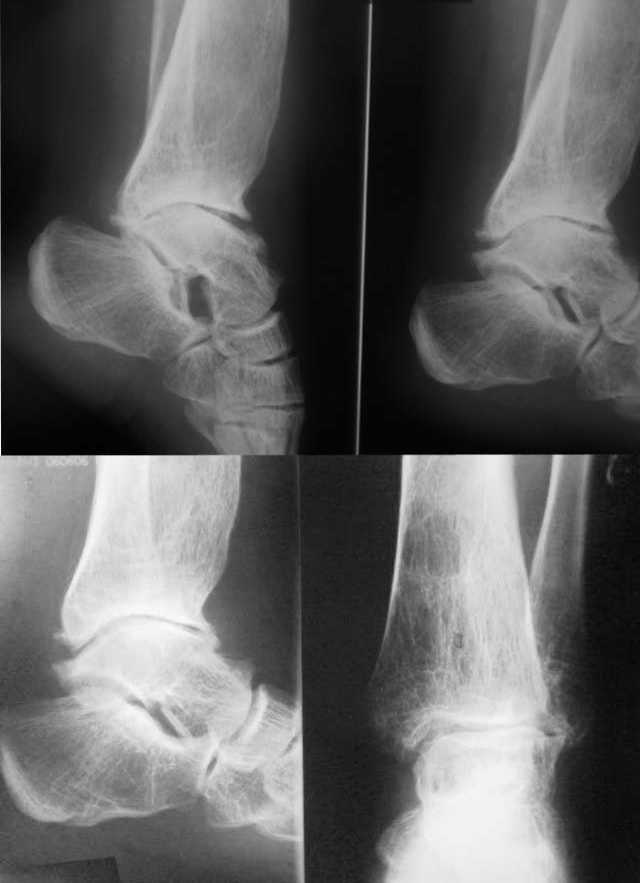

Посттравматическая наружная нестабильность голеностопного сустава у пациентки 30 лет.

Боли не беспокоят. От артродеза отказывается. Боится ограничения движений и хромоты. Как предотвратить наружный подвывих стопы? Может быть кто-то может предложить свою помощь?

Стабилизация за счет пластика из сухожилия большеберцовой мышцы вряд ли ухудшит ситуацию. Но, насколько долго прослужит связка при отсутствии наружной лодыжки?

Больная консультировала свои снимки заочно по интернету в какой-то клинике в Германии. Ей предложили приехать для удлинения малоберцовой кости. Сказали, что операция простая. Больная ищет клинику в России, где бы с такой же уверенностью ей бы пообещали положительный результат. За умеренную цену (или по квоте).